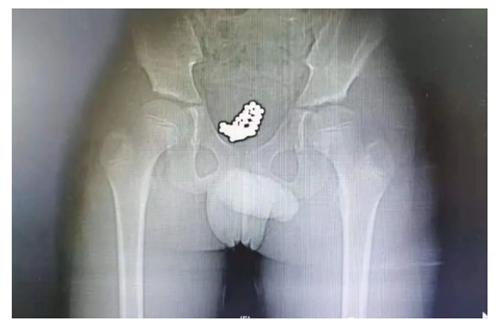

男孩名叫央奇(化名),今年10岁。因尿痛、血尿1天,于7月9日上午10点,由父母带领来到我院看急诊。医生询问病情时,发现小奇全程都低着头,好像试图躲避医生和家长的眼神,只说自己头天下午去游了泳,其他一概支支吾吾、避而不答。随后,医生给他拍了一个CT,一拿到片子就大致猜到是怎么回事了。“从片子可以清晰看到,他的膀胱里充满了一颗颗小珠子,直径大约5毫米 ,估计是不久前塞进去的!”泌尿外科副主任医师刘明分析。

患者的CT片

手术过程中,医生经尿道将输尿管镜推送至膀胱内,镜下见吸附到一起的磁珠体,形似“石榴”,磁珠之间吸附力强大,镜下无法一一分开,只能行膀胱切开异物取出术。术中将吸附在一起的磁珠体完整取出体外,经检查,共计74颗,手术过程顺利,术后恢复良好。